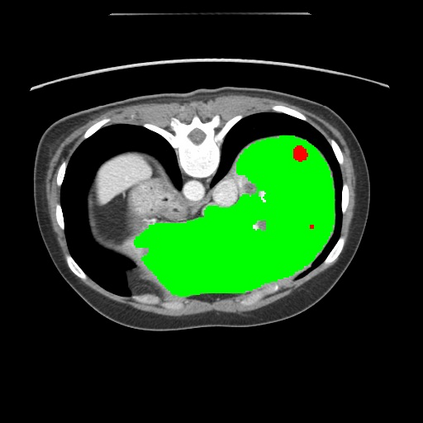

Transformers have made remarkable progress towards modeling long-range dependencies within the medical image analysis domain. However, current transformer-based models suffer from several disadvantages: (1) existing methods fail to capture the important features of the images due to the naive tokenization scheme; (2) the models suffer from information loss because they only consider single-scale feature representations; and (3) the segmentation label maps generated by the models are not accurate enough without considering rich semantic contexts and anatomical textures. In this work, we present CASTformer, a novel type of generative adversarial transformers, for 2D medical image segmentation. First, we take advantage of the pyramid structure to construct multi-scale representations and handle multi-scale variations. We then design a novel class-aware transformer module to better learn the discriminative regions of objects with semantic structures. Lastly, we utilize an adversarial training strategy that boosts segmentation accuracy and correspondingly allows a transformer-based discriminator to capture high-level semantically correlated contents and low-level anatomical features. Our experiments demonstrate that CASTformer dramatically outperforms previous state-of-the-art transformer-based approaches on three benchmarks, obtaining 2.54%-5.88% absolute improvements in Dice over previous models. Further qualitative experiments provide a more detailed picture of the model's inner workings, shed light on the challenges in improved transparency, and demonstrate that transfer learning can greatly improve performance and reduce the size of medical image datasets in training, making CASTformer a strong starting point for downstream medical image analysis tasks.